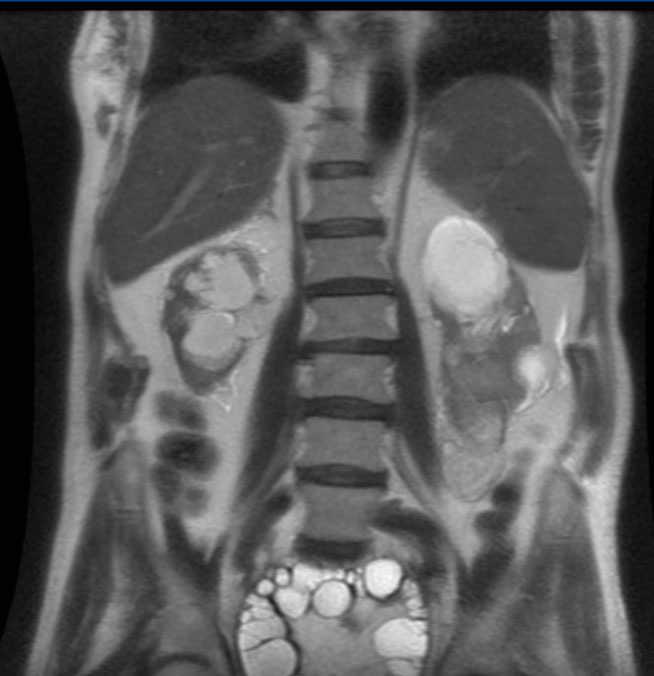

The MRI (Figure 1) showed a large space-occupying lesion of a maximum diameter of 17.5cm invading the pelvic cavity with the upper pole at the height of L4-L5, and almost total collapse of the bladder. It had a well-defined ovoid shape with multiple internal septa, consistent with hydatid cyst of Polat’s II2B type. In the lower pole of the LK, a 61mm ovoid lesion consistent with inactive type III hydatid cyst was observed. There was dilatation of both renal collecting systems, with reduced RK, which had a diameter of 84mm and cortical thinning. The LK had a longitudinal diameter of 11cm.

Figure 1. MRI